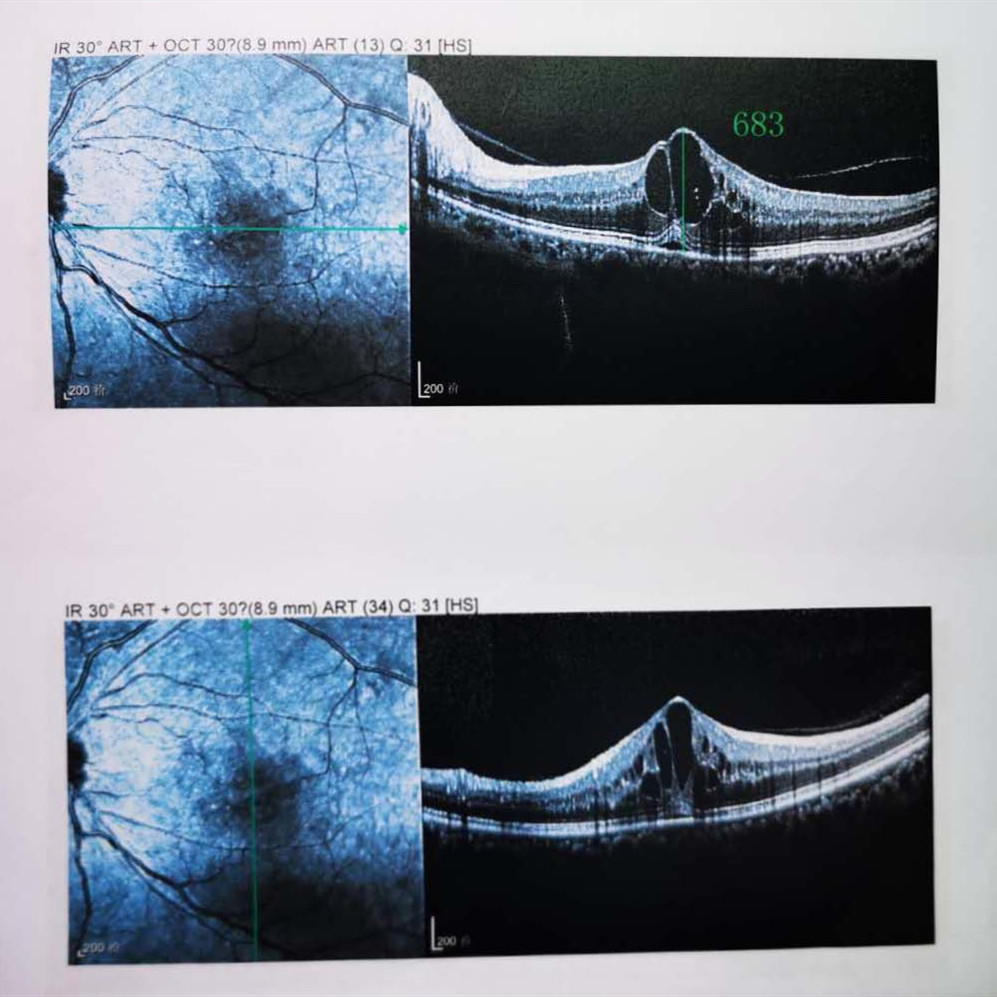

檢查結(jié)果顯示,武先生并沒有近視,右眼視力為1.0,但是左眼視力只有0.4,而且左眼視網(wǎng)膜各分支靜脈迂曲擴張,全網(wǎng)膜面見火焰狀出血,黃斑區(qū)高度水腫、滲出,黃斑中心凹厚度約683um。

(武先生初次就診眼底OCT檢查圖)

而正常的矯正視力是1.0,黃斑中心凹厚度在200um左右。

“你這黃斑都腫到正常人的三四倍大了!”廈門眼科中心吳國基院長醫(yī)生告訴武先生,“你這是左眼視網(wǎng)膜中央靜脈阻塞伴黃斑水腫,你左眼的視力下降、看東西變形,是因為你左眼視網(wǎng)膜的中央靜脈發(fā)生了阻塞、出血,導(dǎo)致眼底黃斑水腫了。”

那么,武先生的視力恢復(fù)情況如何呢?幸運的是,經(jīng)過兩次玻璃體腔注藥術(shù),武先生左眼的黃斑水腫得到明顯改善,視力已經(jīng)恢復(fù)到0.8。

(武先生出院時眼底OCT檢查圖)